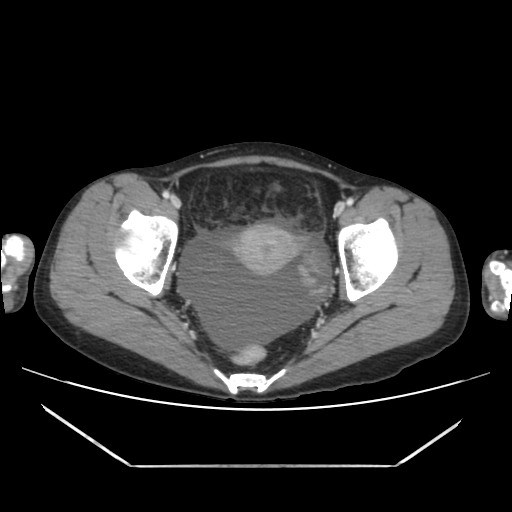

환자의 복부 CT 영상을 환자의 머리쪽에서부터 다리 쪽 방향으로 중간중간 한 컷씩 나열해 보았다.

CT 영상만 보더라도 환자는 괴사성췌장염으로 일부췌장과 주변 조직들이 녹아 있음을 알 수 있고, 이로 인해 복막염, 이차적으로 장마비 소견까지 보이고 있었다.